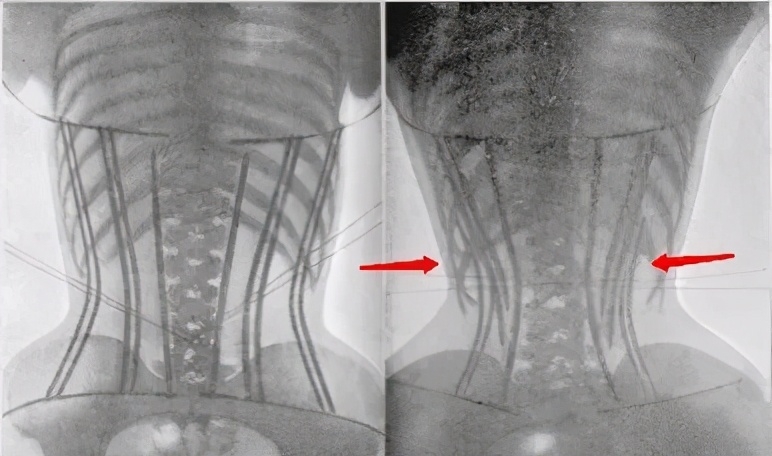

不少女士為了突顯腰線都甘願使用腰封、束腹帶等小工具,不過其實長時間使用束腹帶不但有機會影響骨骼生長,而且更有可能導致腰部或脊椎骨變形,就連正面的肋骨也同樣會被擠壓,嚴重的話更有可能會影響身體裡面的器官,大家絕對要小心使用啊!